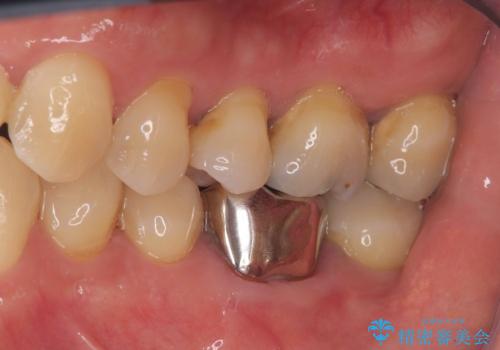

インプラント治療は手術が一度で完了し、術後の痛みもほとんどありませんでした。

機能面・審美面ともに大きく改善され、患者様にも大変ご満足いただけました。